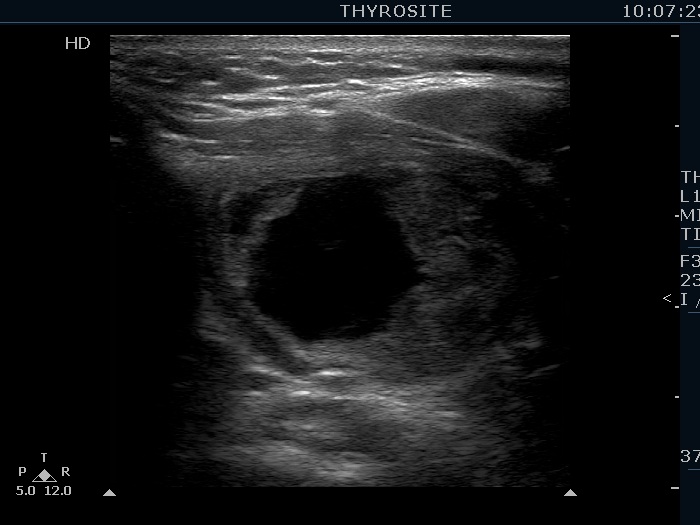

Left lobe, transverse scan - after aspirating 22 mL cystic fluid.